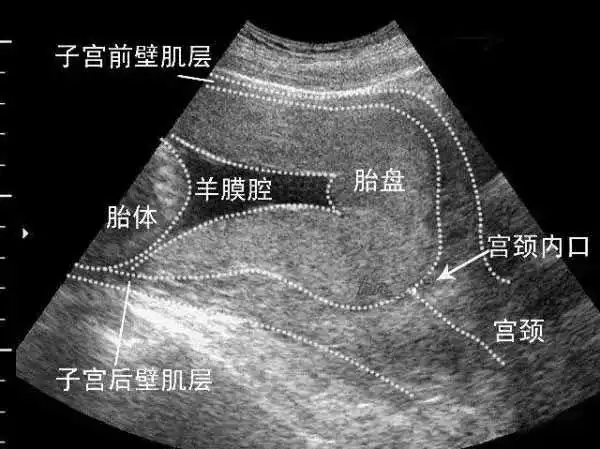

胎盘位置不好?这个数值越小越危险!

孕妇羊水多少正常羊水过多如何处理羊水过多对胎儿有何影响